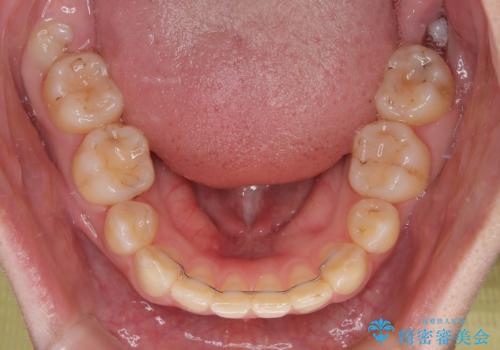

上下の抜歯位置を変えることで、左右ともに理想的な咬み合わせを達成することができました。